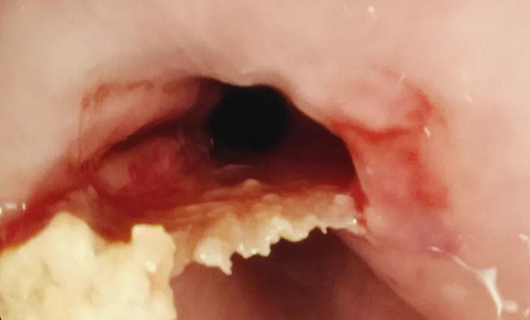

PART3:上切开刀“啃”下硬骨头

小明(化名)一吃东西就“胸痛”,胃镜显示,食道中下段有异物,是一块呈倒三角形的骨头,而且嵌入太深,异物钳夹取失败,鼠齿钳也“啃”不动这块骨头。边鹏想到了切开刀,用调到最高频率的切开刀在骨头最宽处一点一点切出一个豁口,在切开刀作用下,骨头变得松软,豁口处合上时,卡着的骨头松动了,再用异物钳将骨头夹出。